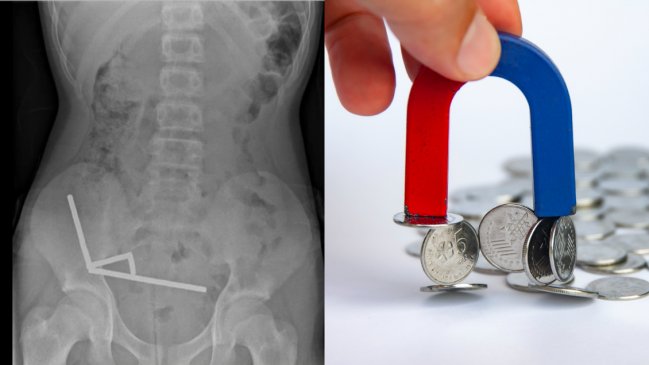

Radiografía y foto referencial de imán

New Zealand Medical Journal / iStock

Según informó el New Zealand Medical Journal, los médicos detectaron mediante una radiografía que varias hileras de imanes se habían adherido dentro del intestino del niño, lo que provocó que distintas secciones quedaran unidas. Esta presión no sólo causó un daño severo en el órgano, sino incluso la muerte de parte del tejido.